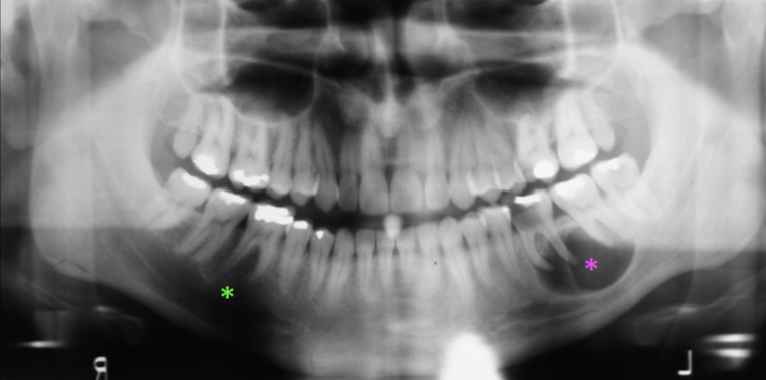

What is the dental anomaly?

Radicular Cyst

Healing Cyst

What are the Radiographic Characteristics of this Healing Cyst?

New bone forms at the original cortex and grows toward the center